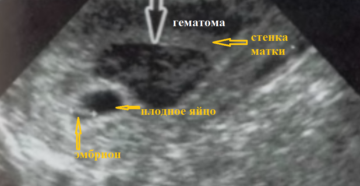

Гематома матки на ранних сроках беременности Каким бы прекрасным ни казалось время беременности, на протяжении…